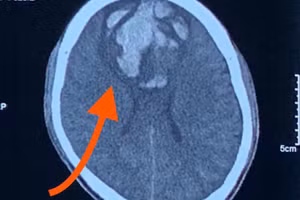

GD&TĐ - Bệnh viện Trung ương Quân đội 108 tiếp nhận nam sinh chấn thương sọ não do chìa khóa cắm sâu ở đầu, xuyên qua xương sọ vào nhu mô não khoảng 3 cm.